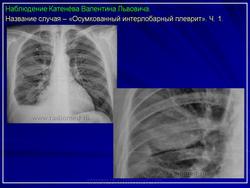

3. Осумкованные интерлобарные плевриты.

Рентгенологическая картина в полной степени зависит от количества экссудата, от локализации, состояния окружающих тканей.

Междолевые осумкованные плевриты являются следствием свободного выпота, как результат «затекания» экссудата в междолевые щели, где и происходит процесс осумкования. Довольно часто процесс осумкования происходит на уровне сердечно-диафрагмальных синусов.

Как правило, исследование только в прямой проекции, не позволяет поставить диагноз. Типичная скиалогическая картина междолевого осумкованного плеврита имеет отображение на боковой рентгенограмме.

Иллюстрации 1, 2. Теневая картина осумкованного выпота в малой междолевой щели.